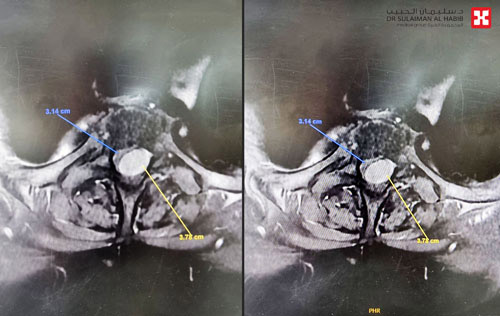

بفضل من الله تمكن مركز طب وجراحة المخ والأعصاب بمجمع الدكتور سليمان الحبيب الطبي بالعليا من إعادة القدرة على الحركة لسيدة في الستين من العمر أقعدها ورم ضاغط على النخاع الشوكي خلف الفقرتين الصدريتين الثانية والثالثة، إضافة إلى أنها عانت من تضيق متوسط الحدة بالقناة الشوكية، وقد أجريت لها عملية جراحية